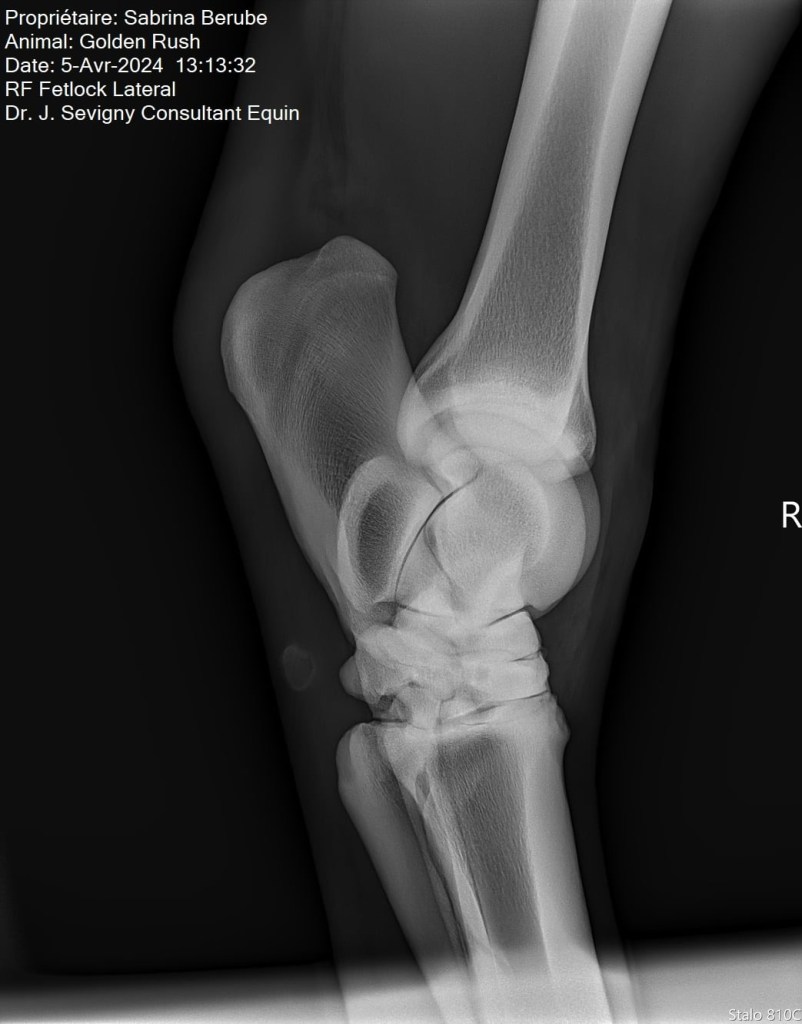

Par la suite, lors de la visite de ma vétérinaire, on a pris des radios de ses jarrets suite à son examen. Il n’a pas répondu tant que ça aux tests de flexion, mais tout de même il y a avait un petit quelque chose. Sur les radios, on a pu constater une présence d’arthrose modérée, ce qui venait expliquer le tout. Rien de surprenant vu son âge et sa discipline par contre, ce qui m’a rassurée un peu, mais je voulais traiter le problème. Je vous laisse les images pour vous donner une idée, je ne suis pas une experte en lecture de radio mais en gros, les espaces dans l’articulation sont sensés faire toute la longueur de l’articulation, mais dans le cas de mon cheval (surtout son jarret droit), l’arthrose est présente et fusionne les parties de l’articulation ensemble.